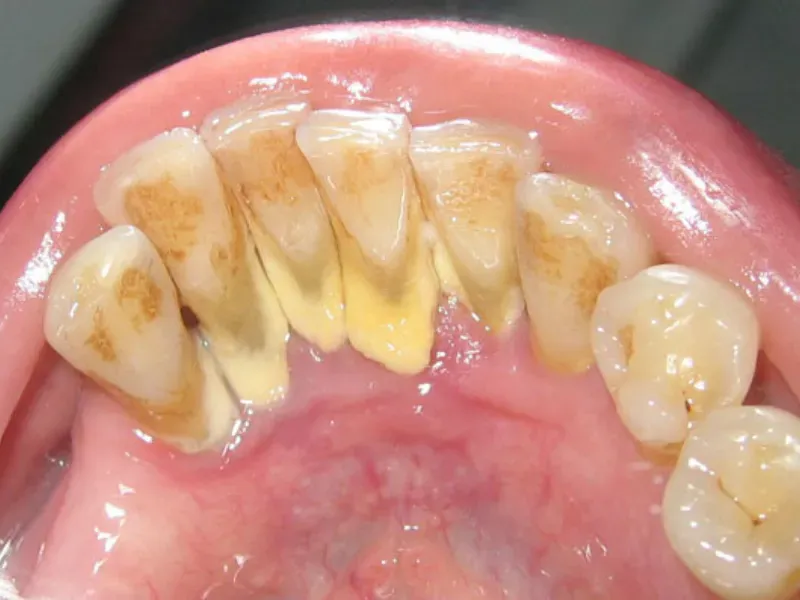

Mảng bám trên răng

Xử lý màng biofilm bằng cách lấy cao răng định kỳ

Khi gặp tình trạng nhiễm khuẩn do màng sinh học gây ra, chúng ta thường sử dụng các phương pháp như: bào láng chân răng, cạo vôi răng, vệ sinh răng miệng tại nha khoa. Các thủ thuật nha khoa sẽ giúp loại bỏ vi khuẩn một cách nhanh chóng bên trong màng sinh học.